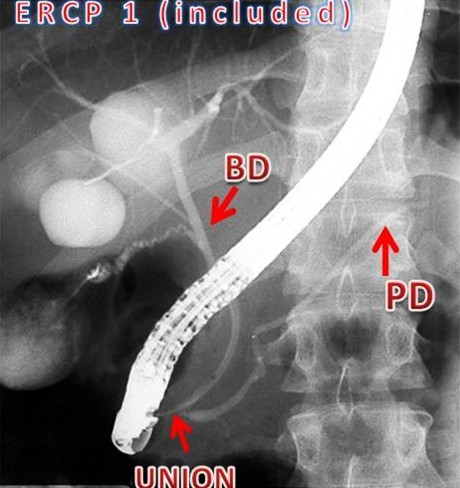

The reporting of the ERCPs was done in a stepwise fashion. The first step was to identify ERCPs in which both ducts were filled and pancreaticobiliary confluence was clearly identified in more than one image (inclusion criteria for study) (Figure 1). ERCPs in which only one duct (pancreatic or biliary) was filled or the confluence of the pancreatic and bile ducts was not clearly visualized were excluded from the study (Figure 1). Second, in those ERCPs included in the study, we then reported on whether the pancreatic and bile ducts opened into the duodenum separately or if the ducts were joined to each other and a common channel opened into the duodenum(Figure 2). Third, we measured the length of the common channel in the latter (Figure 3). To do so, we measured the actual length of the channel as it appeared on the images and corrected it with a magnification factor, as determined by the actual and imagined (as on images) width of the endoscope [15, 21]. If the corrected length of the united duct was less than 6 mm, it was reported as a short common channel. If the corrected length of the united duct was between 6 and 15 mm, it was reported as a long common channel. If the corrected length of the common channel was more than 15 mm, it was presumed that the ductal union had occurred outside the duodenal wall and such patients were reported as having anomalous pancreaticobiliary ductal union [20, 22]. For patients with anomalous pancreaticobiliary ductal union, we determined the pattern and angle of the ductal union. Anomalous pancreaticobiliary ductal union was reported as P-B type when the pancreatic duct appeared to join the bile duct and B-P type when the bile duct appeared to join the pancreatic duct. The angle of union was the actual angle at which the union occurred between two ducts [23].

Figure 1. Step 1 of the present study defined the inclusion and exclusion criteria. Three ERCP images are shown. ERCP 1 (included for further evaluation) shows large hepatic cystic lesions communicating with the bile ducts. Both the pancreatic duct and the bile duct are clearly visualized and the union of the two ducts before entering the papilla is clearly identified. ERCP 2 (excluded from study) shows the malignant stricture of the bile duct. Only the bile duct is visualized. ERCP 3 (excluded from study) from a patient with alcohol-induced chronic pancreatitis. Only pancreatic duct is visualized. BD: bile duct; PD: pancreatic duct. |